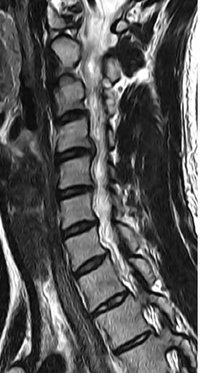

배유지씨의 경추 4·5번, 5·6번 디스크가 탈출돼 있다.

김지희씨의 경추 5·6번 디스크 탈출돼 있다.